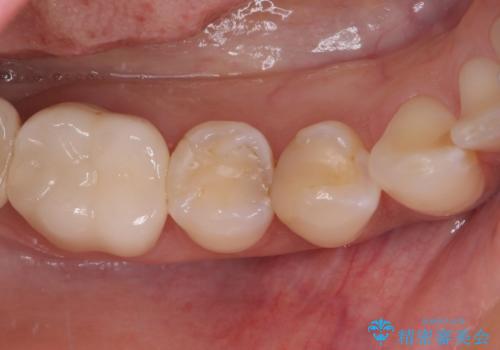

- 冷たいものがしみるとのことで来院された患者様です。

診査を行った結果、第一小臼歯にある樹脂の詰め物(コンポジットレジン)と歯の境目が痛みの原因であることが分かりました。

また、隣接する第二小臼歯も虫歯になっていることも分かったため、2歯を同時に治療するにしました。

下顎の目立つ位置であるため、セラミックインレーによる修復治療を行うこととしました。